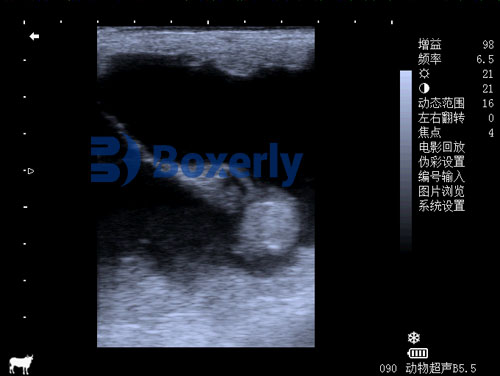

3.1 B-mode Ultrasound Basics

B-mode ultrasound provides grayscale, cross-sectional images of uterine and fetal tissues. High-frequency transducers (5–7.5 MHz for transrectal, 3–5 MHz for transabdominal) are commonly used to balance resolution and penetration.